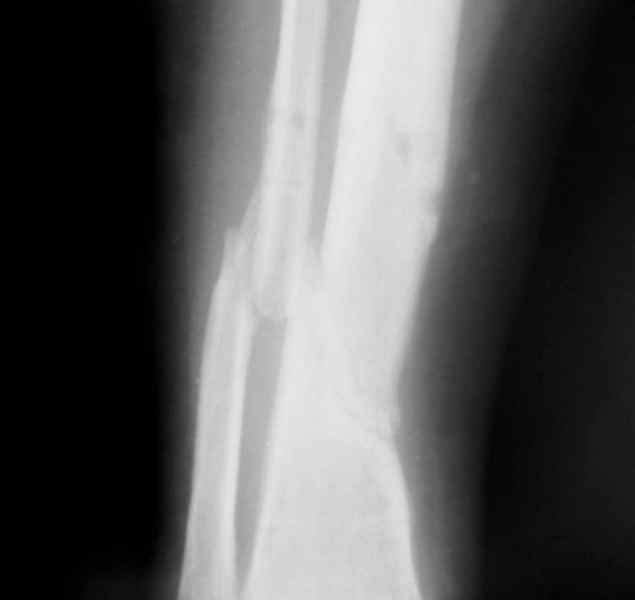

Больная 54 года, 5 м. назад открытый оскольчатый перелом 2-3 тип, Первично ЧКДО, открытое ведение раны, при этапных некрэктомия " ушел" осколок внутренней стенки б/бецовой кости, 7 сутки пластика м/тканями ,вторичные швы.

Контакт отломков только по спирали наружной стенки,заживление раны полное, на 3-4 месяце ЧКДО воздействие на регенерацию микродистрациями , 5 месяц снят аппарат по причине нестабильности и реакции м/тканей. В данный момент проблем с тканями нет, на Р-граммах псевдоартроз, клинически подвижность,больная ходит в ортезе с дозированной нагрузкой.Местно рубцовый процесс 3х5 в зоне перелома.

1. Только штифт первично динамизированныйДостаточно-ли кантакта для сращения?

2.Аддаптирующая резекция через небольшой разрез вне рубца, с оставлением костных фрагментов парадифизарно, как элемент костной пластики, штифт с динамизацией первично (возможно, на начальном этапе + 2 кольца ЧКДО с отсрочкой дистального блокирования)с последующей компенсацией укорочения транспортом на штифте.

В общем - план здравый, м мы бы заштифтовали, но тут важны детали. Стержень взяли бы бесканальный, титановый и потолще (12 мм). Дистальный отломок заперли бы винтами хотя бы тремя, а лучше 4.

Возможно, с poller винтами. "Нестабильность и реакция м/тканей" могут быть недооцененным "спицевым" остеомиелитом. Для профилактики инфекции стабильность надо создать максимальную. Запереть лучше бы статически на первые пару месяцев, динамизировать потом.